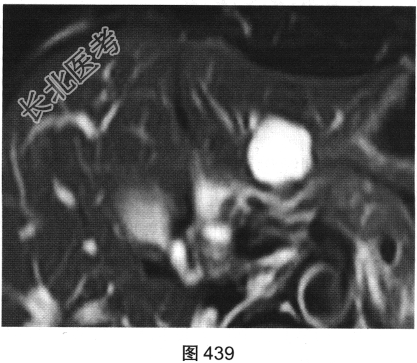

- [材料题] 患者女性,44岁,HBV感染史6年。查体:腹平软,右上腹无压痛,无反跳痛,肝脾肋下未及,Murphy征阴性,肝浊音界存在,肝上界位于右锁骨中线第五肋间,肝区无叩击痛,移动性浊音阴性。实验室检查:肝功能未见异常,AFP(一)。患者MRI平扫如图438、图439所示。

- 多项选择题1.MRI平扫图中可见哪些影像学发现( )

A、T1WI上呈均匀低信号

B、T1WI上呈均匀等信号

C、平扫肝左叶可见一类圆形病变

D、病变与周围分界欠清晰

E、T2WI上呈均匀高信号

F、T2WI上呈均匀低信号